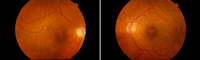

Figura 1. Angiografía fluoresceínica en fase venosa precoz (A y B) y fondo de ojo (C) . En el ojo izquierdo se aprecian las líneas horizontales con franjas hipofluorescentes e hiperfluorescentes correspondientes a los valles y crestas (cortesía Dra. Fossas-Dr. Arruga).